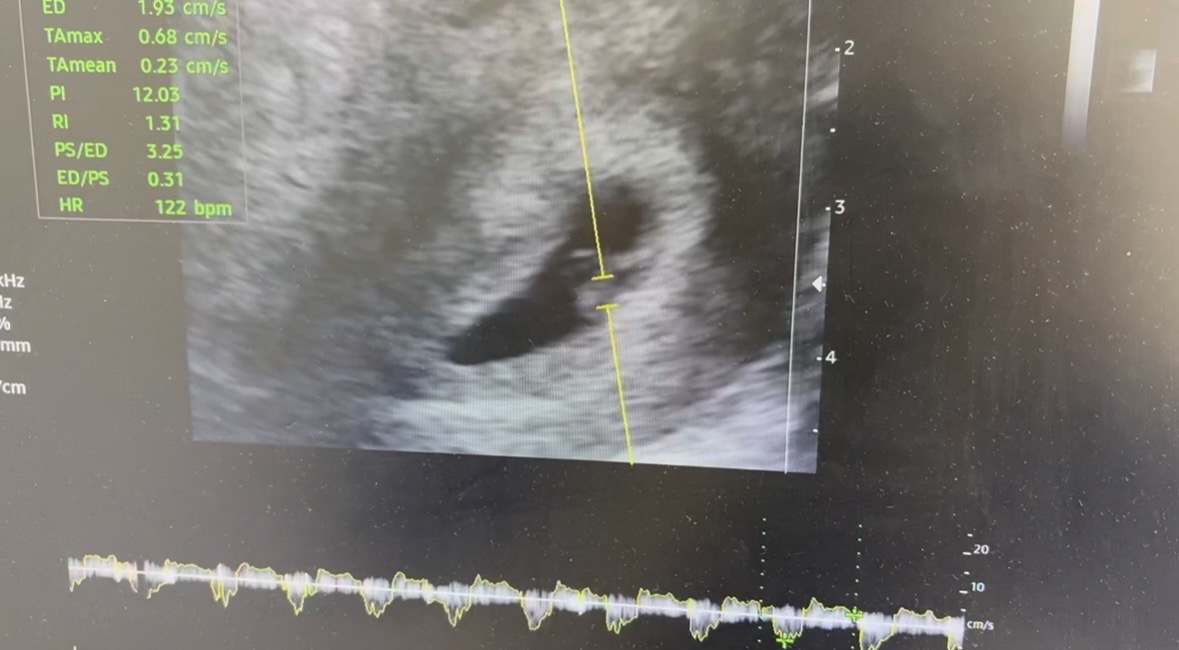

초음파 사진 좀 봐주세요🥲

아기집이나 아기나 다 찌그려서 있는거 같은데 괜찮은건가요? 다른분들은 이기집도 동그랗고 다이아 반지도 예쁘게 보이던데,,